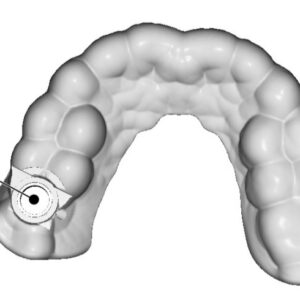

Guías quirúrgicas 3D en Studio Digital Imaging

Las guías quirúrgicas 3D para implantes dentales son herramientas diseñadas para facilitar la colocación precisa de implantes en procedimientos de odontología. Estas guías se crean a partir de imágenes 3D de la boca del paciente, obtenidas mediante técnicas como la tomografía computarizada (CBCT) o escaneos intraorales. Beneficios de las guías quirúrgicas 3D: Precisión: Permiten una...